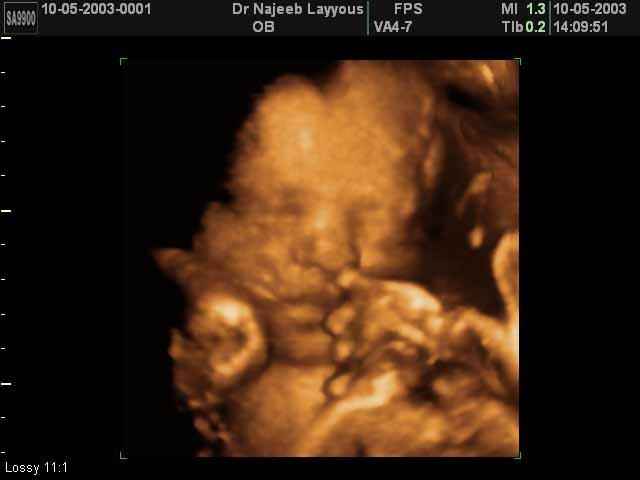

3D Fetal Face Ultrasound Scan Photos